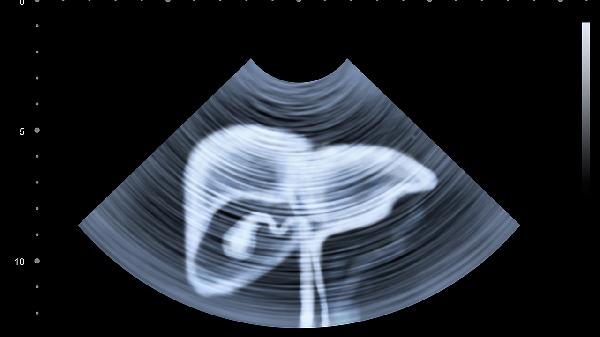

胆囊炎多由胆结石阻塞或细菌感染引发,疼痛常位于右肋弓下缘并向右肩背部放射,伴随恶心、发热等症状。发病可能与高脂饮食、肥胖等因素相关。确诊后需禁食并静脉补液,医生可能开具消旋山莨菪碱片、头孢克肟分散片等解痉抗感染药物,严重者需行腹腔镜胆囊切除术。日常需低脂饮食并规律进食。

病毒性肝炎或酒精性肝炎可导致肝包膜牵张,表现为右季肋区隐痛或胀痛,可能伴随黄疸、乏力。病因包括乙型肝炎病毒感染、长期饮酒等。治疗需根据类型选择恩替卡韦片、水飞蓟宾胶囊等护肝药物,同时绝对戒酒。患者定期监测肝功能,保持高蛋白低脂饮食,避免使用肝毒性药物。